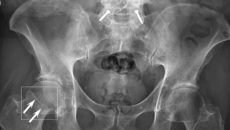

The BoneView software detects potential fractures in X-rays and submits them to radiologists for validation.